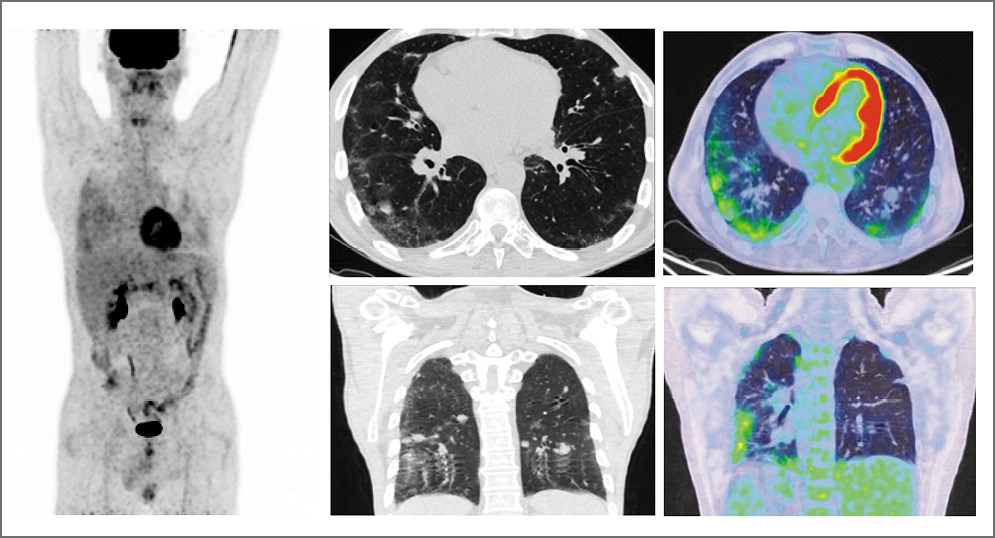

Больной Б. 33 лет. По поводу рака правого яичка выполнена орхифуникулэктомия. При гистологическом исследовании опухоль представлена компонентом семиномы, эмбрионального и с очагами тератоидного рака. При спиральной компьютерной томографии (СКТ) органов брюшной полости с контрастированием обнаружены метастазы в забрюшинные лимфоузлы с максимальными размерами 61×72 мм, со сдавлением нижней полой вены. По данным СКТ органов грудной полости очаговой патологии в легких и средостении не выявлено. Уровень хорионического гонадотропина человека – 3,8 мЕд/мл, альфа-фетопротеина – 175,2 МЕ/мл, лактатдегидрогеназы – 436 ЕД/л. Установлен диагноз: смешанная опухоль правого яичка, стадия IIIА рT2N3M0S1, осложненная синдромом нижней полой вены. Диагноз обсужден на междисциплинарной комиссии. Назначена системная полихимиотерапия по схеме BEP в стационарном режиме в количестве 4 циклов с учетом факторов прогноза. Схема BEP включала в себя 30 мг блеомицина в 1, 3, 5-й дни, 100 мг/м2 этопозида в 1–5-й дни и 20 мг/м2 цисплатина в 1–5-й дни. По окончании 1-го цикла терапии и на протяжении последующих развивалась фебрильная нейтропения. Проводилась поддерживающая терапия гранулоцитарным колониестимулирующим фактором (Г-КСФ). Оценка эффекта лечения не проводилась. Врач самостоятельно увеличил количество циклов до 6. По окончании терапии через 2 нед у пациента появились сухой непродуктивный кашель, одышка в покое, усиливающаяся после физической нагрузки, сильная слабость. Выполнена позитронно-эмиссионная томография, совмещенная с компьютерной томографией (ПЭТ/КТ), с 18F-фтордезоксиглюкозой (18F-ФДГ). В легких с двух сторон определялись зоны неоднородной консолидации легочной ткани с визуализируемыми на этом фоне просветами бронхов, имеющие преимущественно субплевральное расположение, а в нижних долях – перибронхиальное. Эти изменения больше выражены в левом легком с метаболической активностью ФДГ SUVmax=3,70 (рис. 1).

Рис. 1. Пациент Б., 33 года. На ПЭТ, аксиальных и корональных ПЭТ- и КТ-проекциях в легких с двух сторон определяются зоны неоднородной консолидации легочной ткани с визуализируемыми на этом фоне просветами бронхов, имеющие преимущественно базальное субплевральное расположение, в нижних долях – перибронхиальное. Больше выражено в левом легком с метаболической активностью ФДГ (SUVmax=3,70).